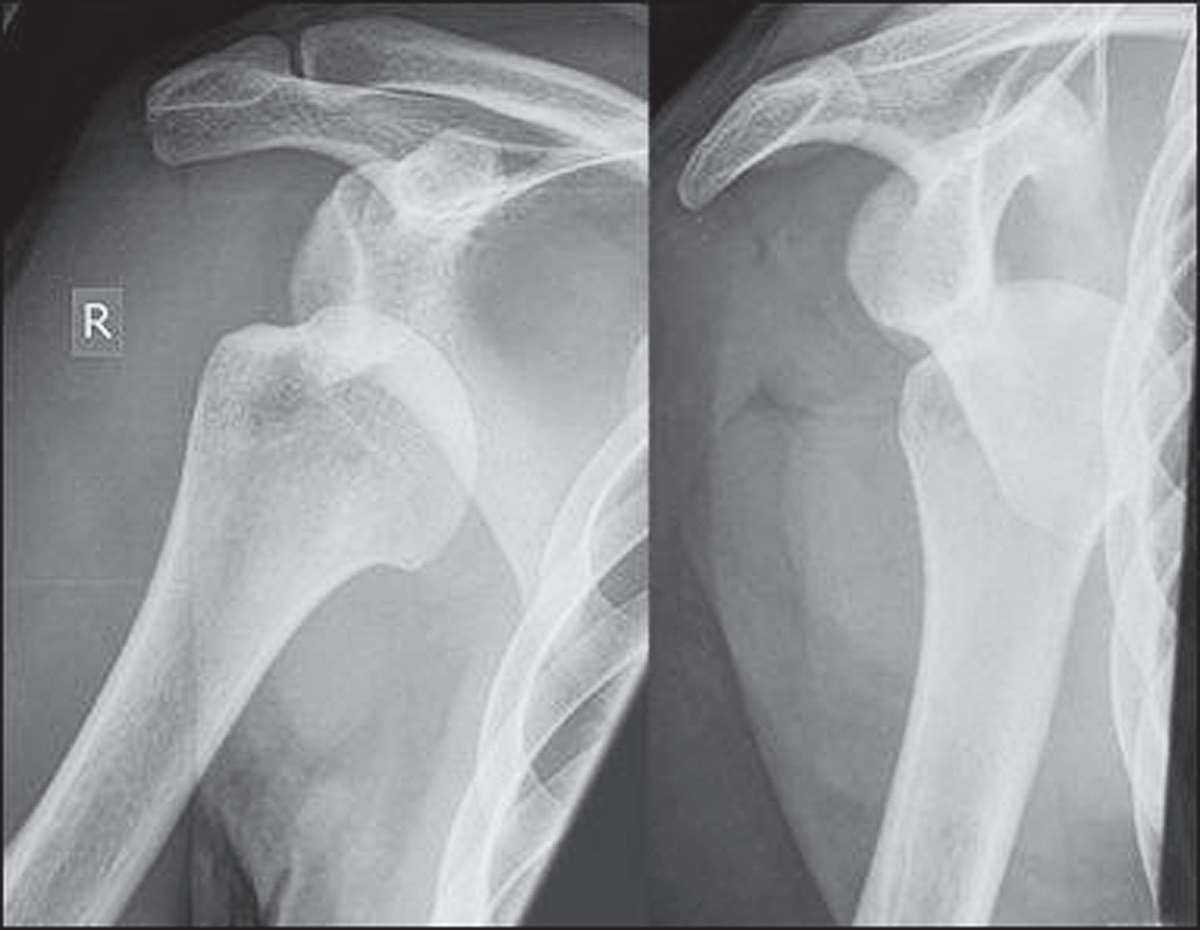

3.影像学检查(图3-1)。

图3-1 肩关节脱位X线片